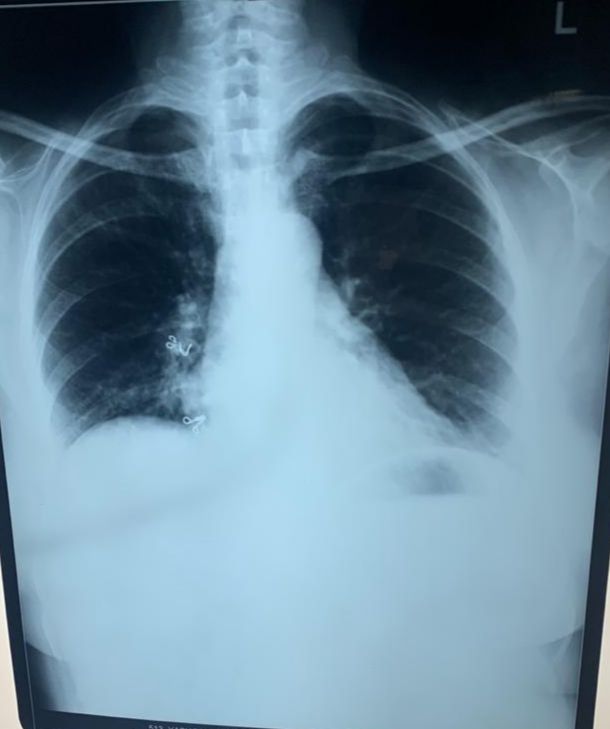

Xray showing money bag appearance indicating pericardial effusion

Xray after 6 months of treatment

Resolution of pericardial effusion